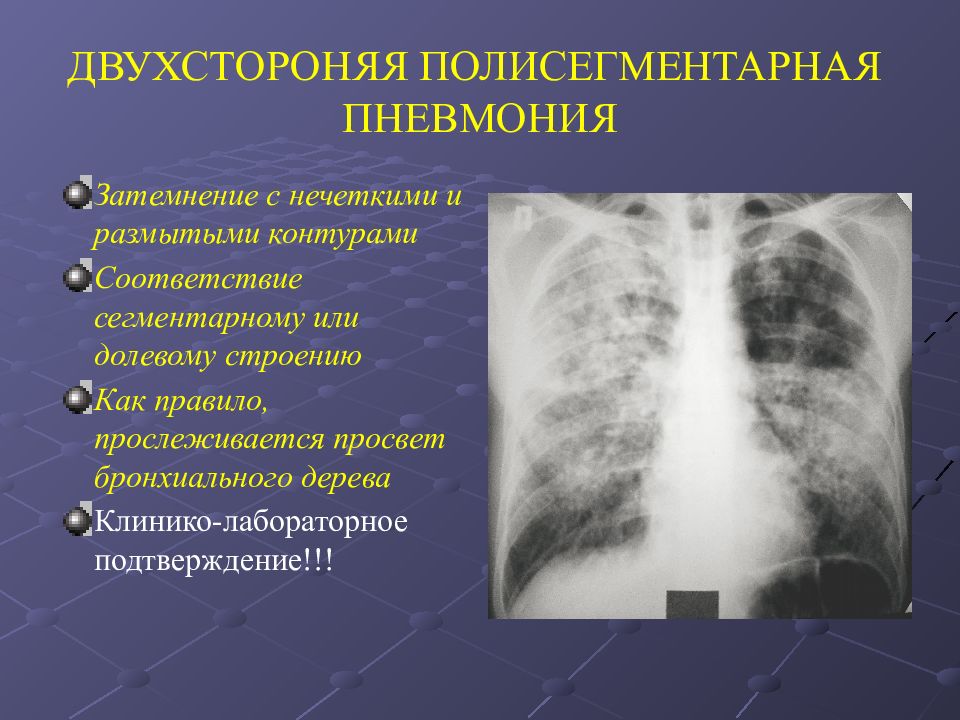

Рентгенологические изображения и синдромы патологии легких

Раздел: Кадры-подсказки